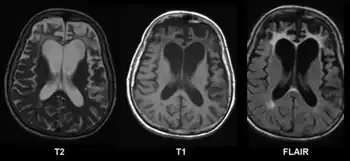

Brain CT with different grading systems of cerebral atrophy (seen as decreased size of gyri and secondary increased size of sulci):[19]

- Medial temporal lobe atrophy (MTA)

- Posterior atrophy (PA)

- Frontal cortical atrophy (fGCA)

CT and MRI are most commonly used to observe the brain for cerebral atrophy. A CT scan takes cross sectional images of the brain using X-rays, while an MRI uses a magnetic field. With both measures, multiple images can be compared to see if there is a loss in brain volume over time.[20]